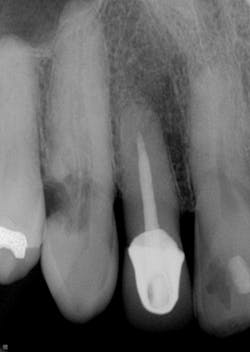

This actually has a huge bearing on dealing with resorption. External resorption versus internal resorption—when diagnosing, it makes all the difference. In my hands (and heart), I believe the only type that stands any chance whatsoever of treatment success is internal resorption. And even then, it depends on the extent of the damage.

When evaluating and discussing external resorption, I commonly tell my patients, “I cannot make your bones and gingiva stop eating the tooth. I do not have that power.” As we have all seen, external resorption can occur in various places and teeth. However, it almost always seems to be around the area of the alveolar crest, which, in my opinion, makes restoring it almost impossible. At least with internal resorption, one has a chance. You must be aggressive in cleaning the canal way beyond the typical endo and particularly in the areas of the defect. That, my friends, is where the microscope comes in very handy.

Unless it is caught on the early end, it does not matter. Once the resorptive damage has extended beyond a certain point, the prognosis drops precipitously, regardless of whether it started internally or externally. If communication of the defect occurs from internal to external or vice versa, I find that the prognosis goes from questionable to hopeless.